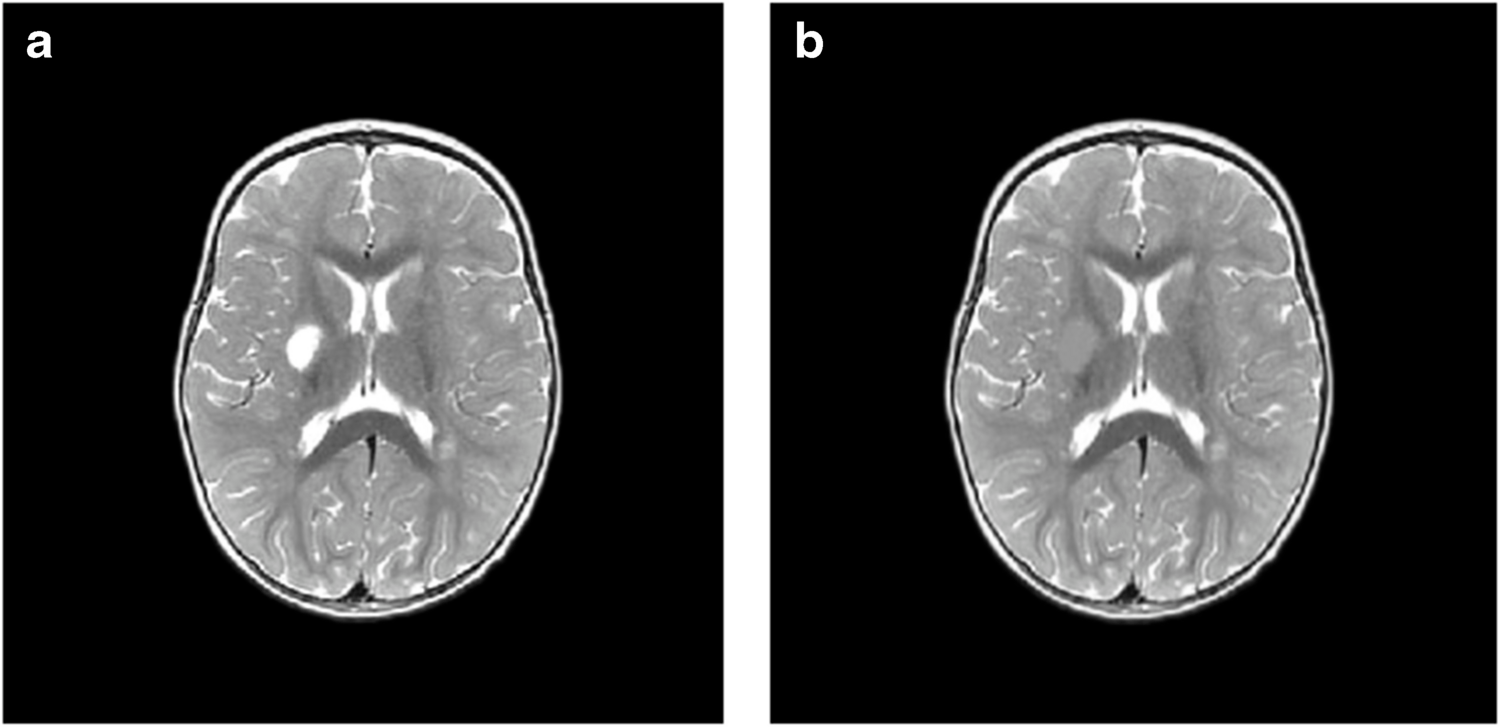

Исследователи проанализировали данные МРТ 35 детей, которые перенесли ишемический инсульт в возрасте до двух лет и лечились в больницах Екатеринбурга, Перми, Челябинска и Тюмени в период с 2015 по 2019 год. Возраст детей на момент инсульта варьировался от четырех дней до одного года 11 месяцев.

Для оценки последствий инсульта исследователи применили современный метод анализа снимков — воксель-базированную морфометрию. Упрощенно эту технологию можно представить так: на каждом МРТ-снимке слой за слоем вручную обводят контуры повреждений области мозга, а специальная компьютерная программа затем вычисляет точный объем этой зоны в кубических миллиметрах. Такая технология позволяет получить наиболее объективные данные по сравнению с традиционным МРТ-отчетом, направленным на определение качественных характеристик (точных границ инсульта, его локализации). Воксель-базированная морфометрия позволяет получить количественные данные: абсолютный и относительный объем поражения от общего объема мозга. Результат применения такого метода — точные числовые значения для последующего статистического анализа и сравнения.

Оказалось, что инсульты у младенцев и детей, достигших месячного возраста, различаются и по масштабам, и по характеру повреждений. Так, у малышей с перинатальным инсультом объем повреждения мозга оказался намного серьезнее, чем у старших: 7,9% против 1,6% от объема мозга. Также у новорожденных чаще встречались нарушения, затрагивающие кору мозга, смешанные и двусторонние инсульты, а у группы детей от 28 дней до двух лет преобладали локальные подкорковые очаги и повреждения только левого полушария.